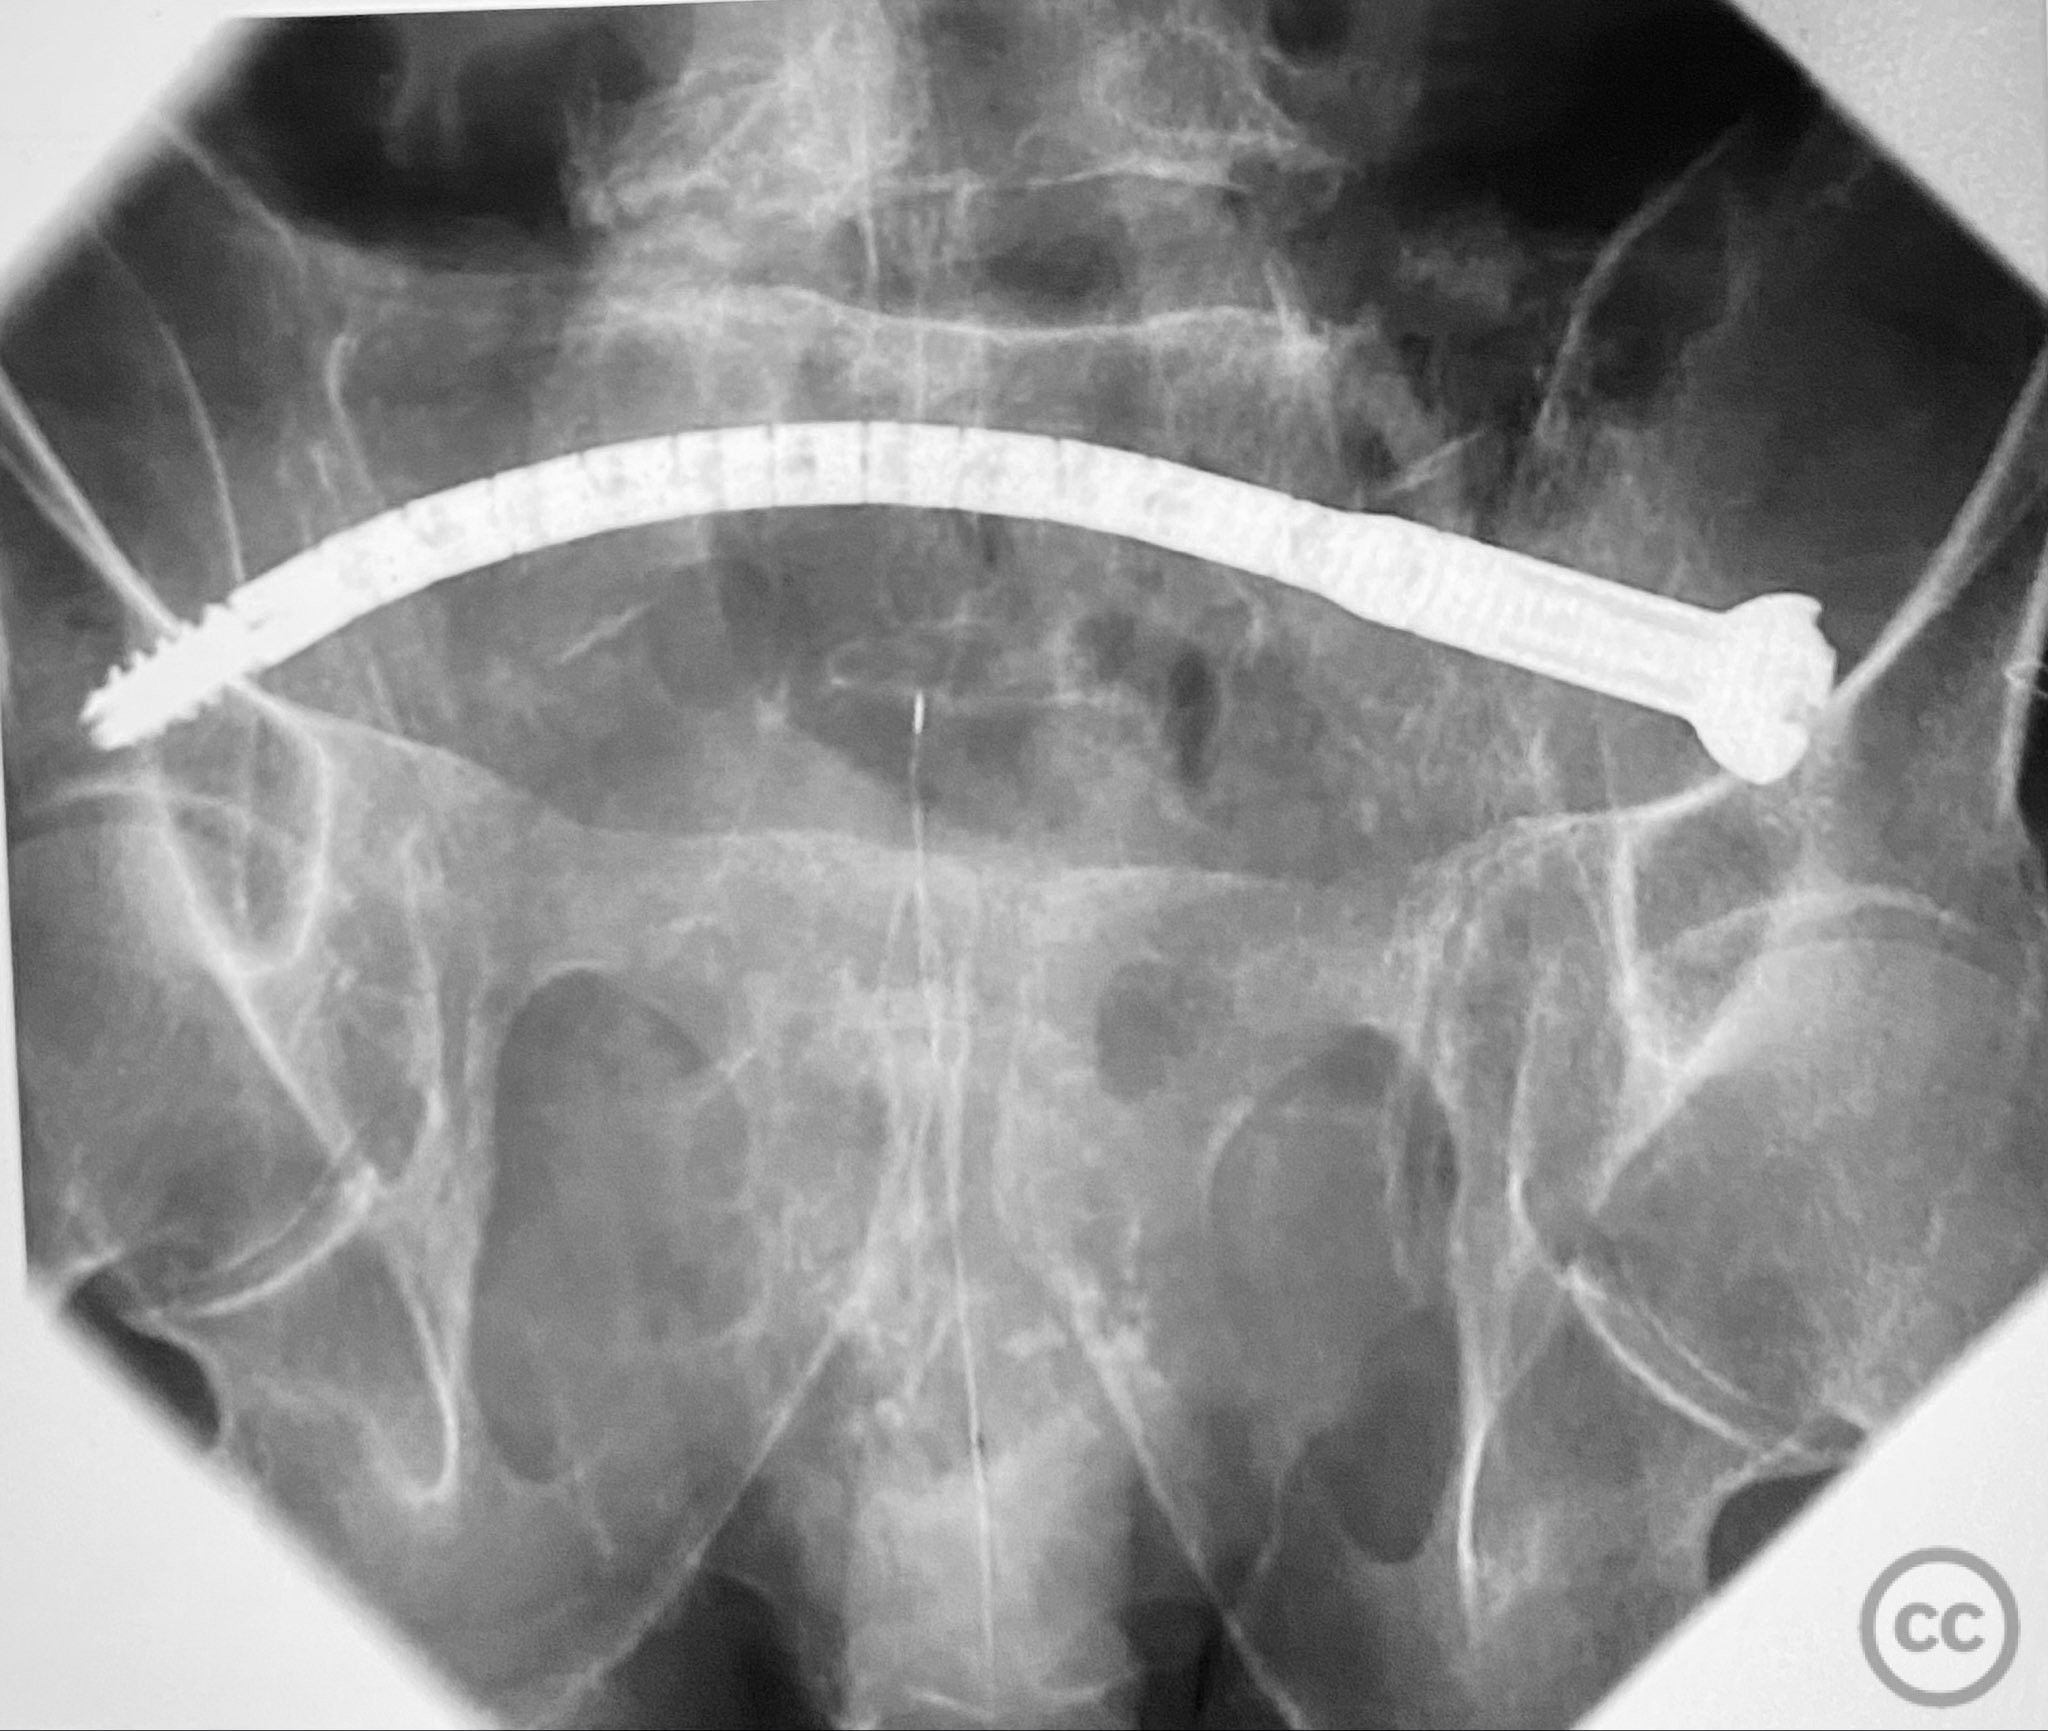

Planning remarks:  The preoperative plan involved percutaneous stabilization of the bilateral oblique upper sacral fractures using a cannulated, articulated intramedullary fixation device (CurvaFix). The anatomical approach was planned to accommodate the oblique trajectory of the sacral fracture pathways, with bilateral guide pin placement under fluoroscopic guidance, followed by device insertion and locking.

Patient positioning:  The patient was positioned supine on a radiolucent operating table to facilitate fluoroscopic imaging in multiple planes (anteroposterior, inlet, and outlet views) for accurate guide pin and device placement.

Anatomical surgical approach:  Percutaneous access was established over the dorsal aspect of the pelvis. Small incisions were made lateral to the sacrum, and soft tissue dissection was performed to the level of the os sacrum. Guide pins were advanced under fluoroscopic control along the oblique upper sacral corridors bilaterally. The cannulated CurvaFix device was inserted over each guide pin, articulated to match the oblique fracture pathway, and subsequently locked in situ according to the manufacturer’s specifications.

The articulated nature of the CurvaFix device allowed precise accommodation of the complex oblique upper sacral fracture pathways bilaterally. Percutaneous technique minimized soft tissue disruption and surgical morbidity. Postoperative CT imaging confirmed satisfactory device placement and fracture reduction. The achieved stability provided immediate pain relief, reduced or eliminated narcotic requirements, and enabled early mobilization. Surgeons with experience in device removal have reported no technical difficulties.